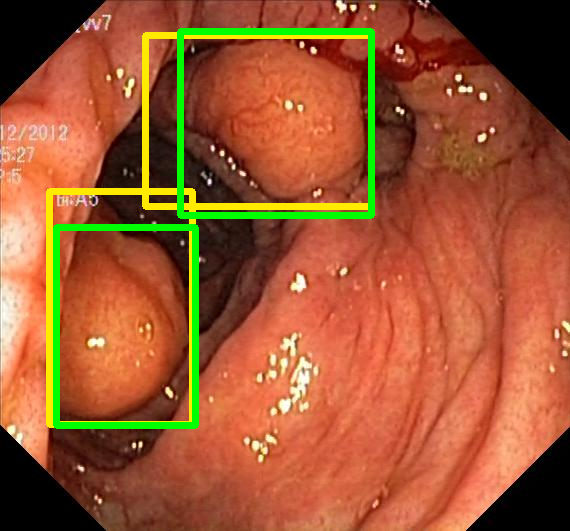

We evaluate the resulting object detection models using the test data, which is pre-processed in the same manner as the validation data, with AP@[.5:.95] (AP for conciseness), AP@.5 (AP50), and AP@.75 (AP75) computed for predicted bounded boxes with a confidence score \geq0.05. For all metrics, a higher value indicates better performance. The results are presented in Table VI, and some examples for predicted bounding boxes with a confidence score \geq0.5 are shown in Fig. 1.

Figure 1: Targets (yellow bounding boxes) and predictions (green bounding boxes) for two randomly selected instances of the Kvasir-SEG test set. For conciseness, we denote ResNet50s with RN, ViT-Bs with VT, Hyperkvasir-unlabelled with HK, ImageNet-1k with IN, MoCo v3 with MC, Barlow Twins with BT, MAE with MA, supervised pretraining with SL, and no pretraining with NA-NA.